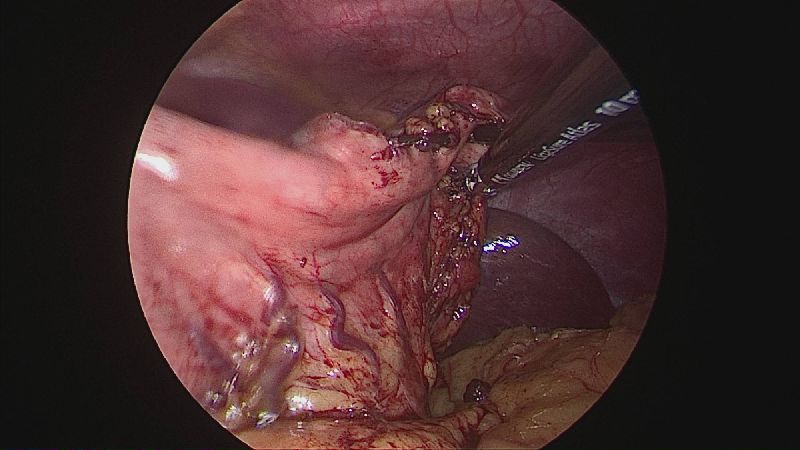

Operația ”de micșorare a stomacului” se realizează miniminvaziv (laparoscopic) și constă în îndepărtarea marii curburi gastrice cu păstrarea antrului gastric și a micii curburi sub forma unui tub calibrat pe o sondă.